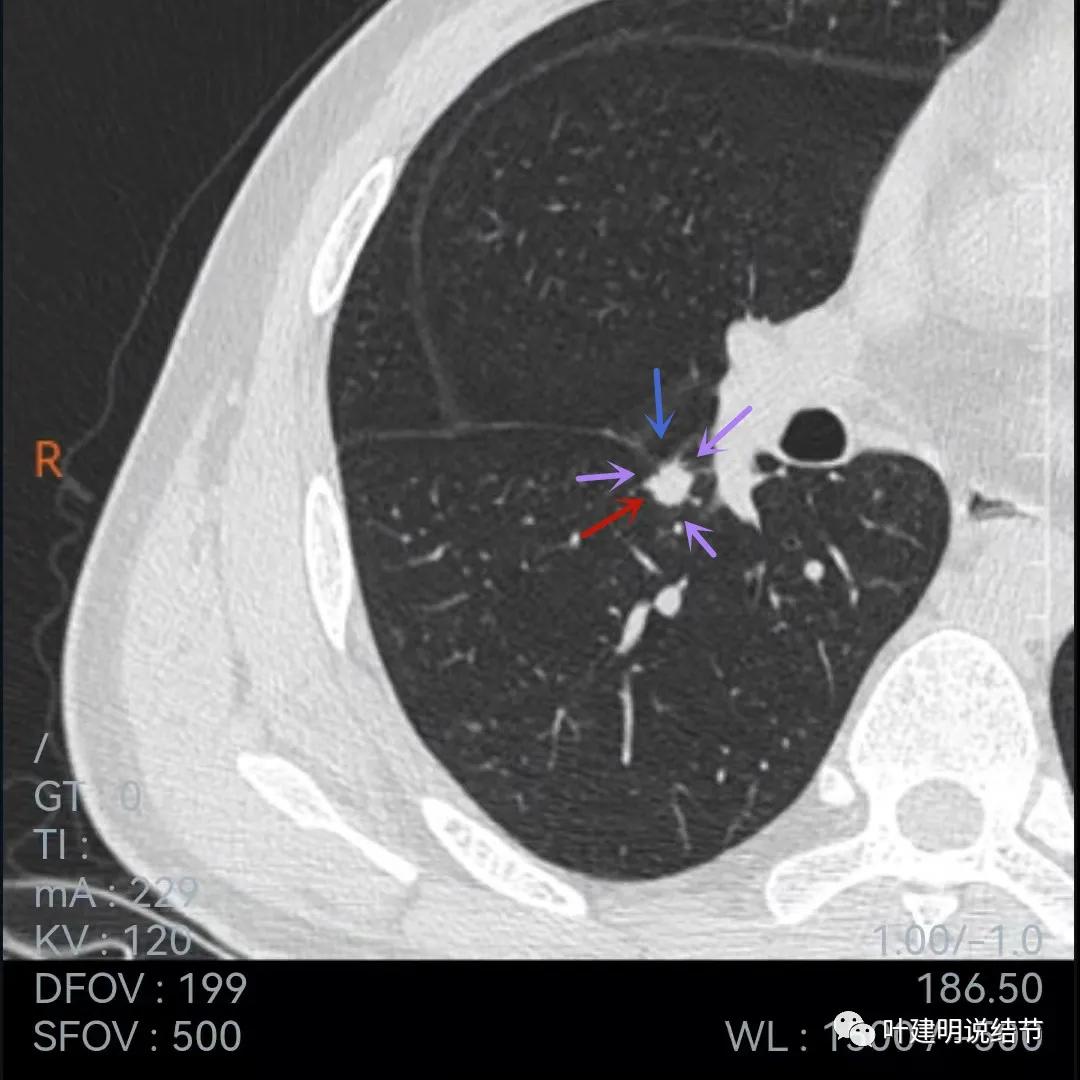

再来看薄层的,今年的薄层是1毫米一层的,去年是2毫米:

病灶胸膜凹陷更明显了,边缘不太平整(紫色箭头)

胸膜牵拉,伴病灶中间密度稍低

病灶膨胀性不够,感觉刺突相对较长,中间密度略低,边缘向内凹

上图黄色箭头示病灶中间密度要略低于周边部位,这与肉芽肿较为符合

整体还病灶似有进展,形态略有变化,但说典型的恶性样子好像又不太像。